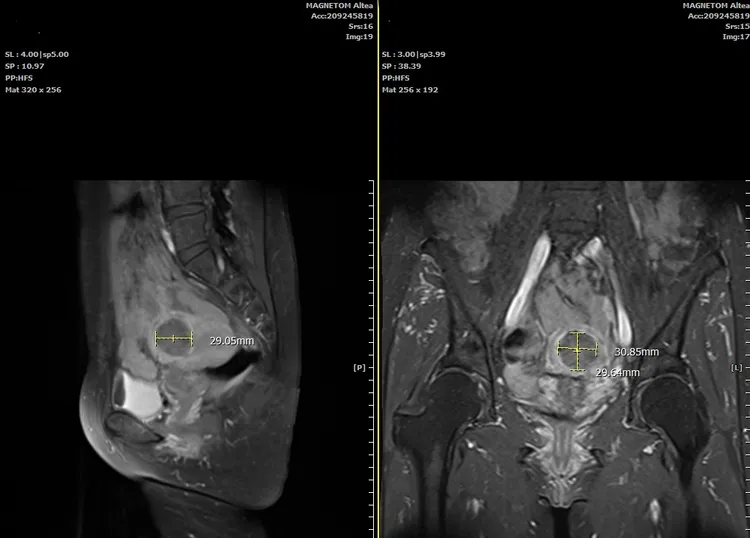

劉錦成主任說,患者還沒進入更年期階段,溝通後建議可進行海芙刀無創手術治療。當天門診立即安排手術時間,採用2天1夜方式輕鬆治療,手術執行僅個多小時就成功完成,經由術前及術後核磁共振影像檢查,明顯看出原本5公分左右的子宮肌瘤縮小到3公分。

吳姓患者術後回診進行MRI檢查,肌瘤經無創海芙治療消融後,逐漸被周圍正常組織吸收縮。童綜合提供